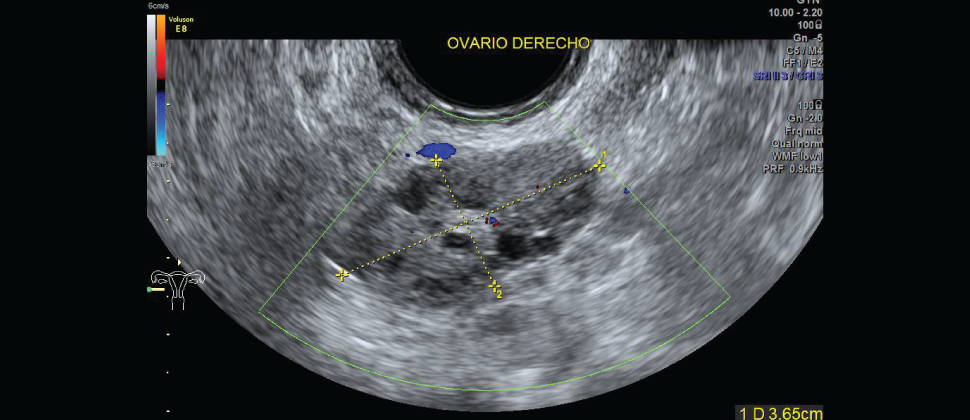

Es un procedimiento de ultrasonido transvaginal, generalmente se realiza primero para observar el endometrio, o las paredes del útero, incluyendo su grosor y toda anormalidad ovárica relacionada.

El examen por ultrasonido transvaginal se realiza en forma muy similar a un examen ginecológico e implica la inserción de un transductor en la vagina luego de que la paciente vació su vejiga. La punta del transductor es más pequeña que la del espéculo estándar que se usa para realizar una prueba de Papanicolaou.